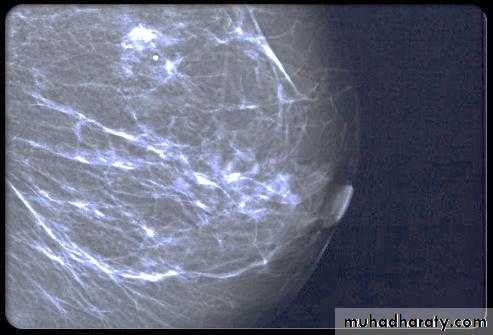

Mammogram

Mammography

Mammography is a dedicated radiographic technique for imaging the breast. An x-ray (radiograph) is a noninvasive medical test that helps physicians diagnose and treat medical conditions. Imaging with x-rays involves exposing a part of the body to a small dose of ionizing radiation to produce pictures of the inside of the body.

The mediolateral oblique (MLO) view is one of standard mammographic views. It is the most important projection as it allows to depict most breast tissue.

The craniocaudal view (CC view), is one of the two standard projections in a screening mammography. It must show the medial part as well the external lateral portion of the breast as much as possible.